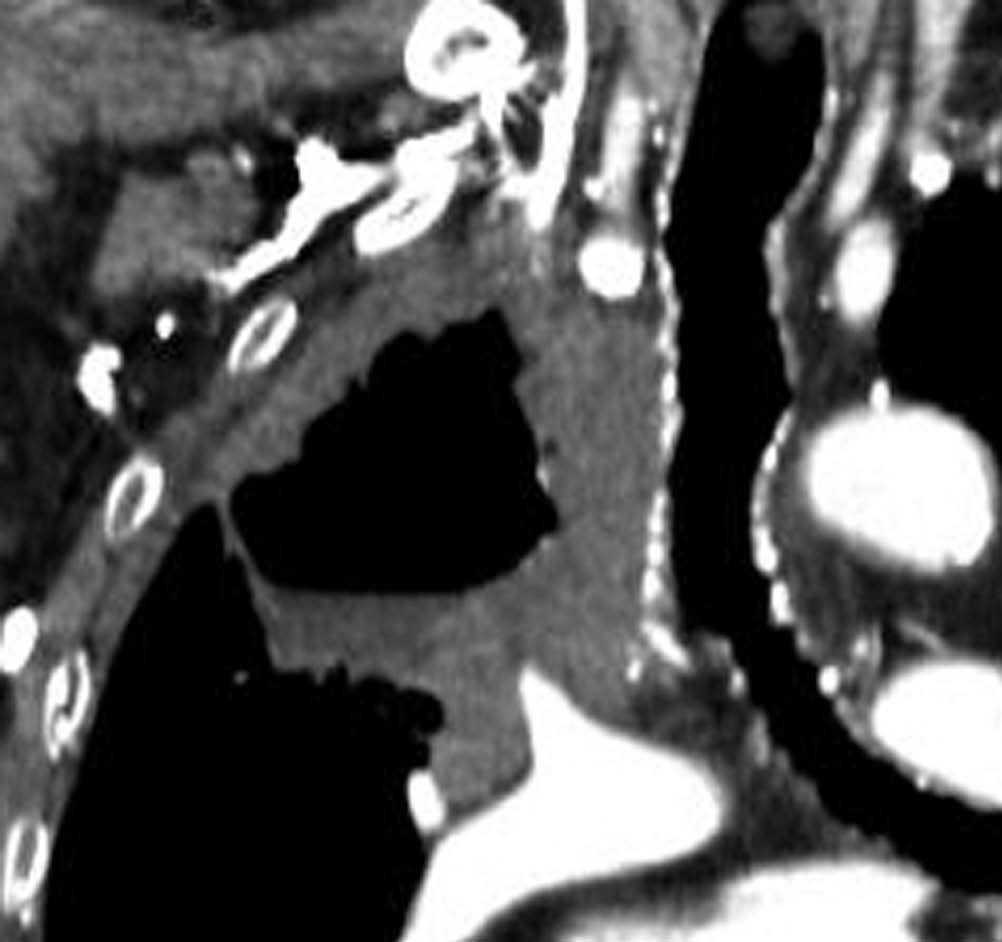

El estadio tumoral (T) se basa en el tamaño, localización y relación con las estructuras adyacentes valorado mediante TC. Los tumores T1 son aquellos de 3 cm o menores en su diámetro mayor, rodeados de pulmón y que no invaden la pleura visceral ni los bronquios principales, mientras que los T2 son lesiones mayores de 3 cm, o aquellas que invaden la pleura visceral o al bronquio principal a más de 2 cm de la carina o que condicionan atelectasia o neumonitis obstructiva que no afecte a todo el pulmón. La diferenciación entre ambos estadios tumorales suele ser sencilla mediante TC, salvo la afectación de la pleura visceral, aunque esta no tiene un impacto importante en el manejo clínico. El tumor T3 viene determinado por la infiltración de estructuras vecinas potencialmente resecables, como la pared torácica, diafragma, pleura mediastínica, pericardio parietal o si el tumor está situado a menos de 2 cm de la carina (fig. 1). Los tumores T4 son aquellos que no pueden ser resecados porque engloban a estructuras vitales, invaden el corazón, grandes vasos, esófago o cuerpos vertebrales (fig. 2) o en los que existe un nódulo o nódulos en el mismo lóbulo del tumor. Además de definir la T, es importante reflejar las particularidades de la infiltración de estructuras en vecindad que puedan modificar la actitud terapéutica. Por ejemplo, cambiará la estrategia quirúrgica según el tipo de bronquio afecto o la estructura mediastínica infiltrada, si es sólo la grasa, o un vaso; cuando existe neumonitis o atelectasia secundaria a un tumor central, la planificación del campo de radioterapia dependerá del límite entre la masa y la repercusión pulmonar.

Fig. 2.--T4. (A) Corte axial de tomografía computarizada (TC) torácica con contraste. Tumor hiliar derecho que infiltra la arteria pulmonar derecha, la vena cava superior y engloba al bronquio intermediario. (B) Reconstrucción coronal oblicua, longitudinal al eje de la arteria pulmonar derecha, que muestra cómo engloba el tumor a la rama del truncus superior (flecha blanca) e inferior (flecha negra).